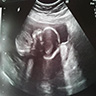

25. oktober ifølge tidlig UL :)

25. oktober :)